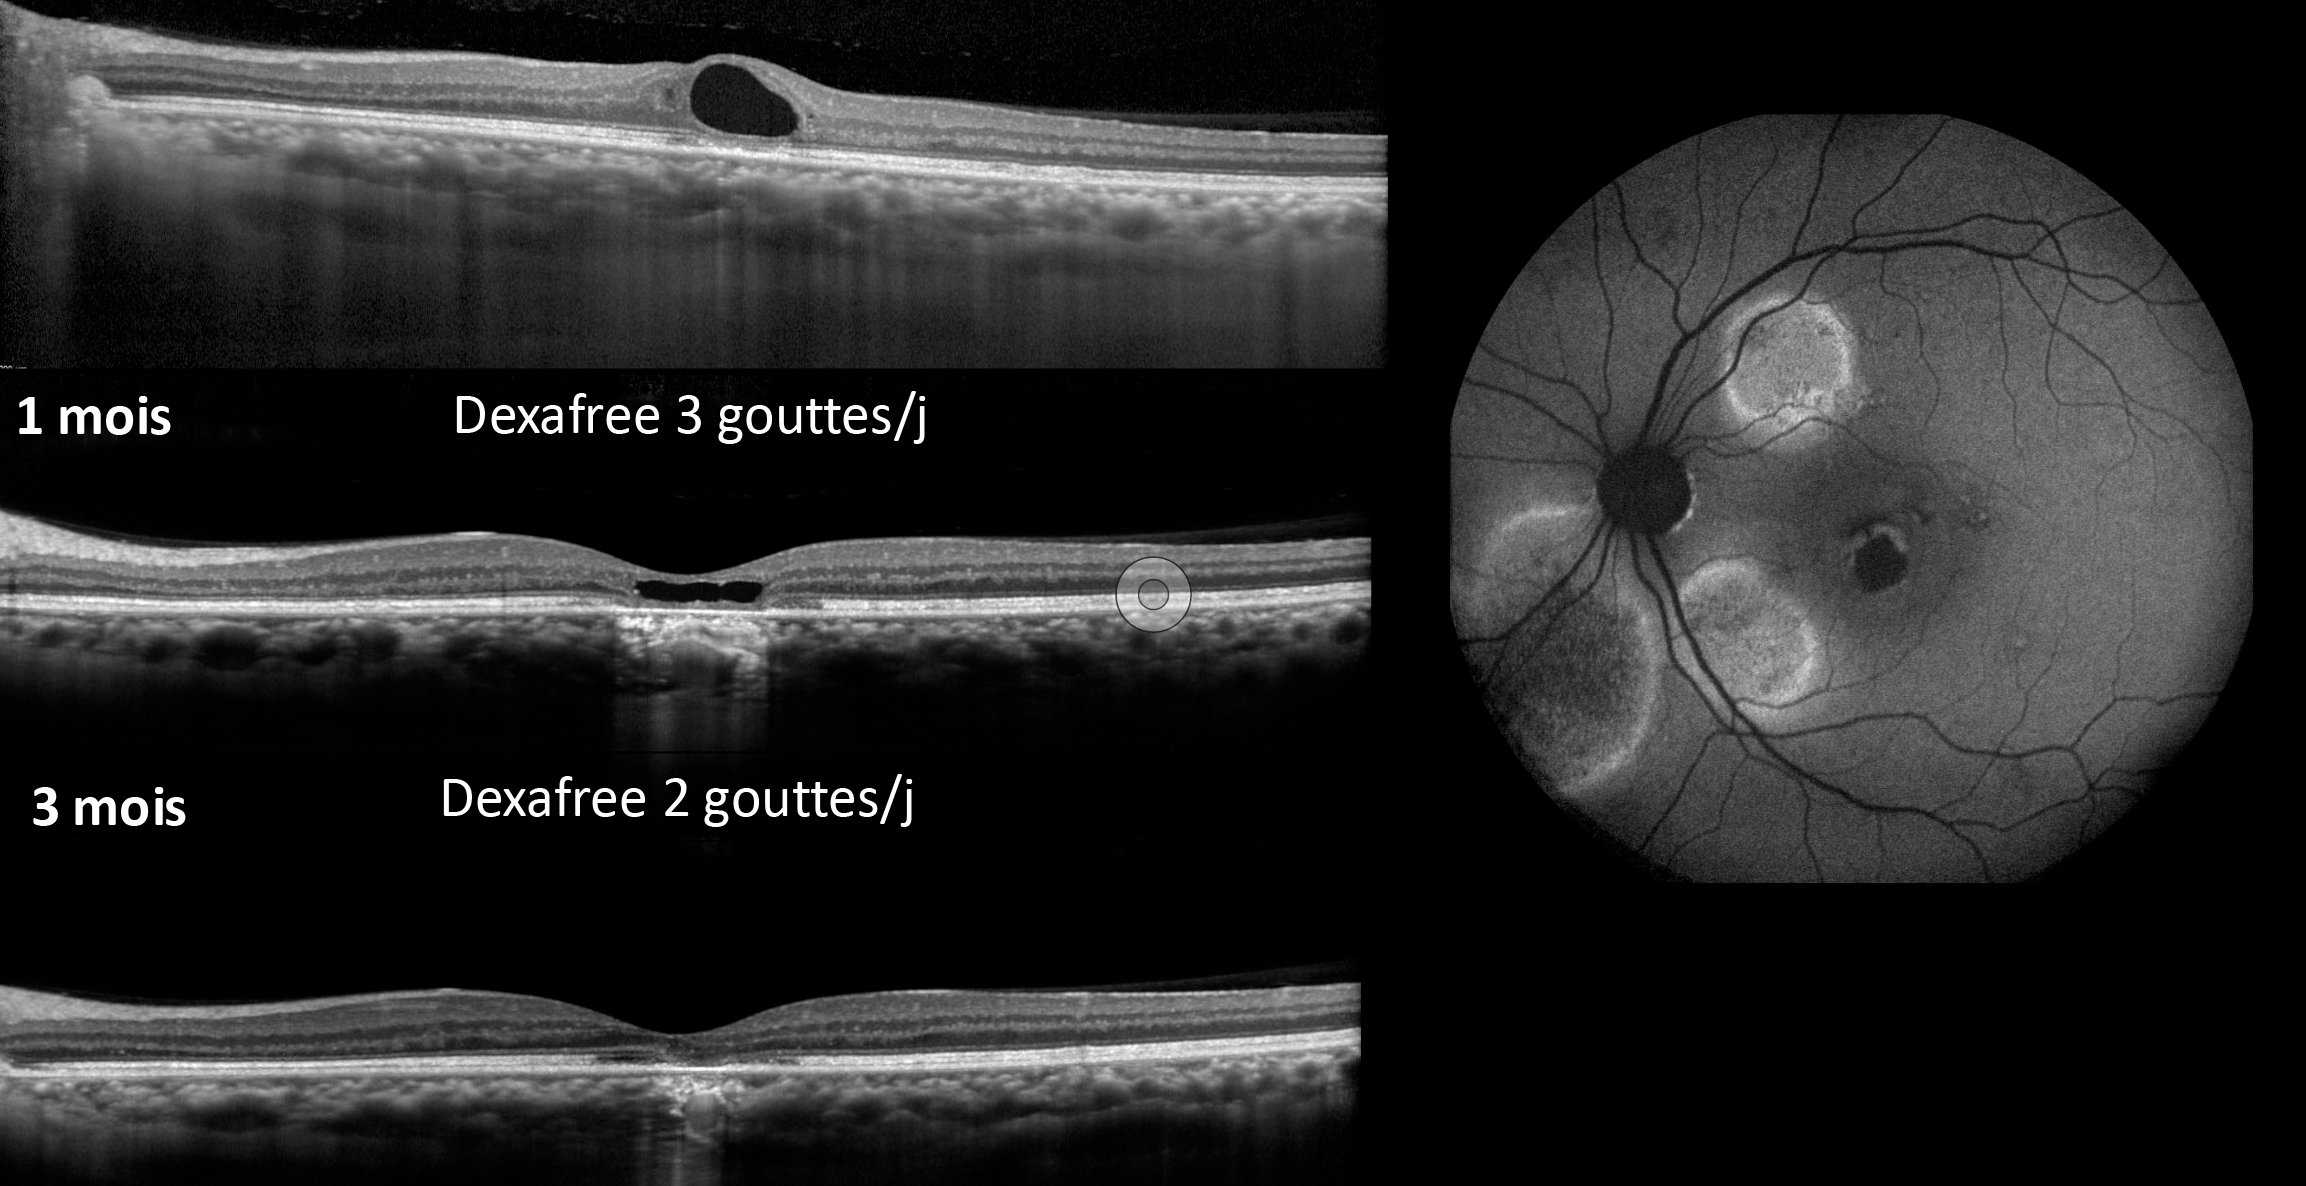

Quand arrêter le traitement de la DMLA néovasculaire ?

Figure 1. Évolution vers l’atrophie d’un néovaisseau de type 3. Bien que l’activité néovasculaire du néovaisseau soit bien maîtrisée avec le traitement, l’acuité visuelle a progressivement diminué à cause de l’atrophie sous-jacente.